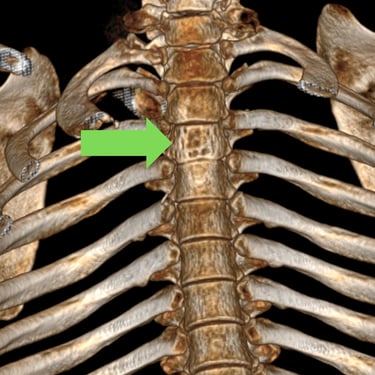

Tumor vertebral dorsal hemorrágico: descompresión medular, biopsia y artrodesis dorsal

El tumor vertebral dorsal puede ocasionar compresión de la médula espinal, dolor intenso y alteraciones neurológicas progresivas. En algunos casos, estos tumores presentan componente hemorrágico que incrementa la presión sobre las estructuras nerviosas. El tratamiento quirúrgico puede incluir descompresión medular para liberar la médula espinal, toma de biopsia para establecer el diagnóstico histopatológico y artrodesis dorsal con instrumentación para estabilizar la columna vertebral. Este abordaje permite reducir el riesgo de daño neurológico, aliviar los síntomas y mantener la estabilidad vertebral. La cirugía se realiza con técnicas especializadas que buscan preservar la función neurológica y mejorar la calidad de vida del paciente.